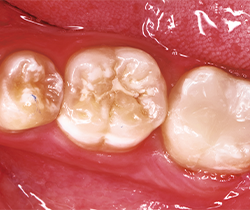

A 14-year-old patient presented to our office for a new patient examination. He had just completed orthodontic treatment and he had several large posterior caries and areas of defective enamel on his anterior and posterior teeth (Figs. 1-5). After a thorough examination and consultation with the patient and father, it was determined that the large caries on teeth #14DO, 18OB and 31OB should be sealed with large fillings, the defective enamel be treated with CTx4 toothpaste and CTx3 oral rinse (CariFree), and monitored as he gets older. The patient was appointed for caries removal and direct restorations to be placed at his next visit.

Fig. 1 Fig. 2